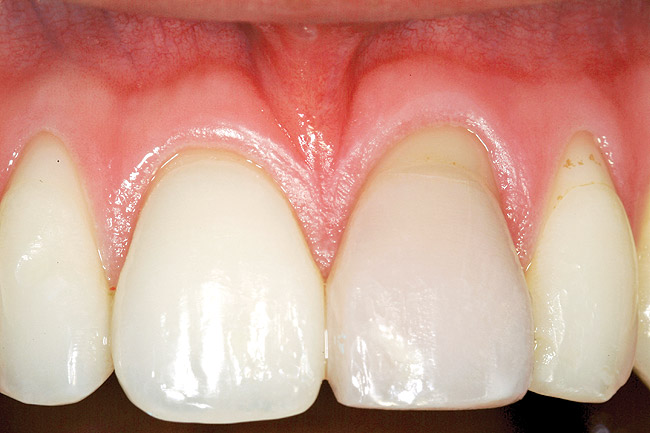

A 54-year-old non-smoking woman presented for correction of deep-wide gingival recession in the maxillary anterior (Figure 1 through Figure 3). The patient’s desires were to correct the gingival recession, balance the heights of contour of the tissues, and possibly undergo esthetic enhancement of the maxillary anterior with veneer restorations.

The 2-month postoperative view can be seen in Figure 13 through 15. Note the color match of the tissue, balance of the facial heights of contour, and zones of attached keratinized tissue present.

Figure 2  Case One Pretreatment clinical view, Case 1, maxillary anterior.

Figure 2

Figure 14  Case One The 2-month postoperative view, maxillary anterior.

Figure 14